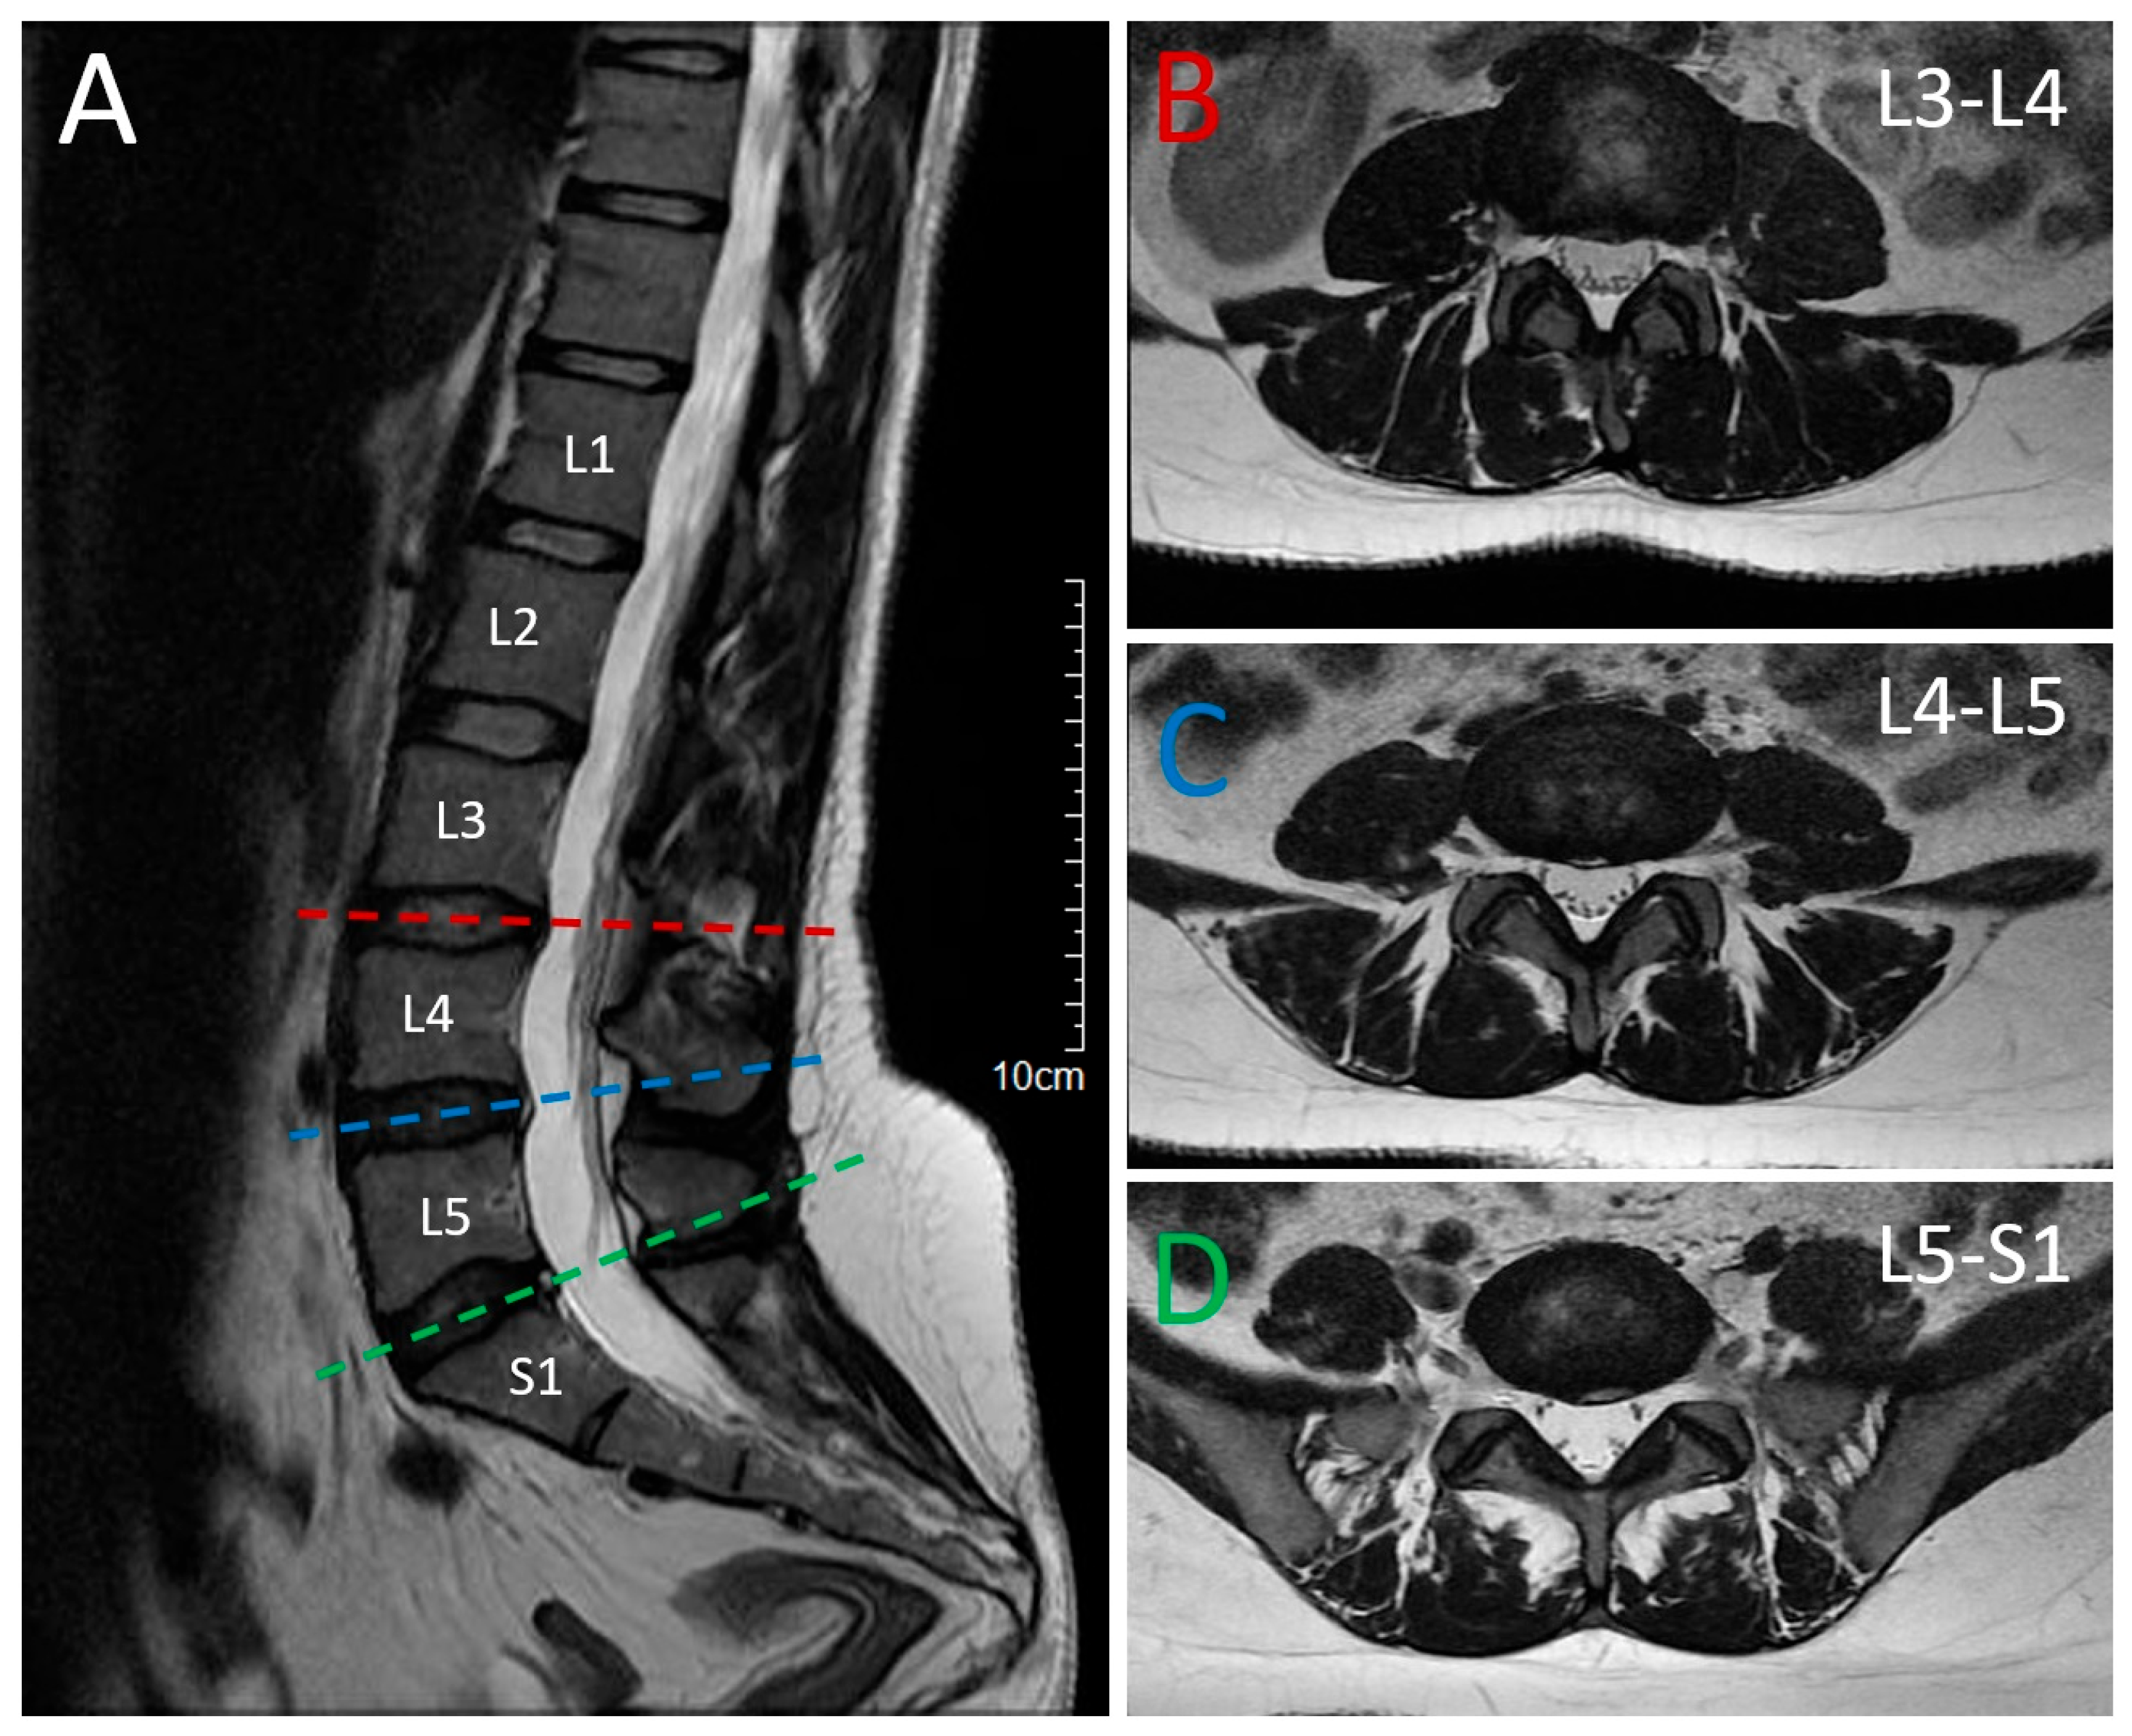

2.1. Patient 1 (Proband)

2.2. Patient 2 (Affected Sibling)